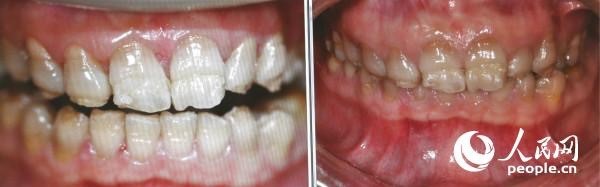

四環(huán)素牙治療前后對比圖 (人民網(wǎng)記者張希 攝)

人民網(wǎng)北京9月20日電 今天為“全國愛牙日”,記者就牙齒健康問題采訪了蓋德口腔國際醫(yī)療中心醫(yī)療總監(jiān)、牙周與美學(xué)修復(fù)專家李秀紅。李醫(yī)生提到,四環(huán)素牙是因為四環(huán)素進(jìn)入人體之后,分布于各個器官和組織,被牙齒吸收之后與鈣作用,形成四環(huán)素與鈣的復(fù)合物。牙釉質(zhì)發(fā)育需要鈣質(zhì),而四環(huán)素與鈣結(jié)合會導(dǎo)致鈣質(zhì)的缺失,這會導(dǎo)致牙釉質(zhì)發(fā)育不全,俗稱“四環(huán)素牙”。李醫(yī)生介紹,四環(huán)素牙是六七十年代較為常見的疾病,隨著四環(huán)素的使用減少,八、九十年代后四環(huán)素牙少見。四環(huán)素牙由于釉質(zhì)發(fā)育不全,容易磨損,出現(xiàn)深的黃或青、灰的牙本質(zhì)顏色,影響美觀。

如何治療四環(huán)素牙呢?李秀紅介紹說:“在以前,改善四環(huán)素牙顏色的常見方法是做烤瓷牙。即把病人的牙齒磨小并為其戴上烤瓷牙套,這種方法對牙齒有一定傷害,甚至?xí)䲟p傷牙神經(jīng)。現(xiàn)在四環(huán)素牙可以通過美白的方法改善顏色問題,對牙齒沒有傷害,牙齒也不會出現(xiàn)敏感,疼痛。”(實習(xí)生李星星)